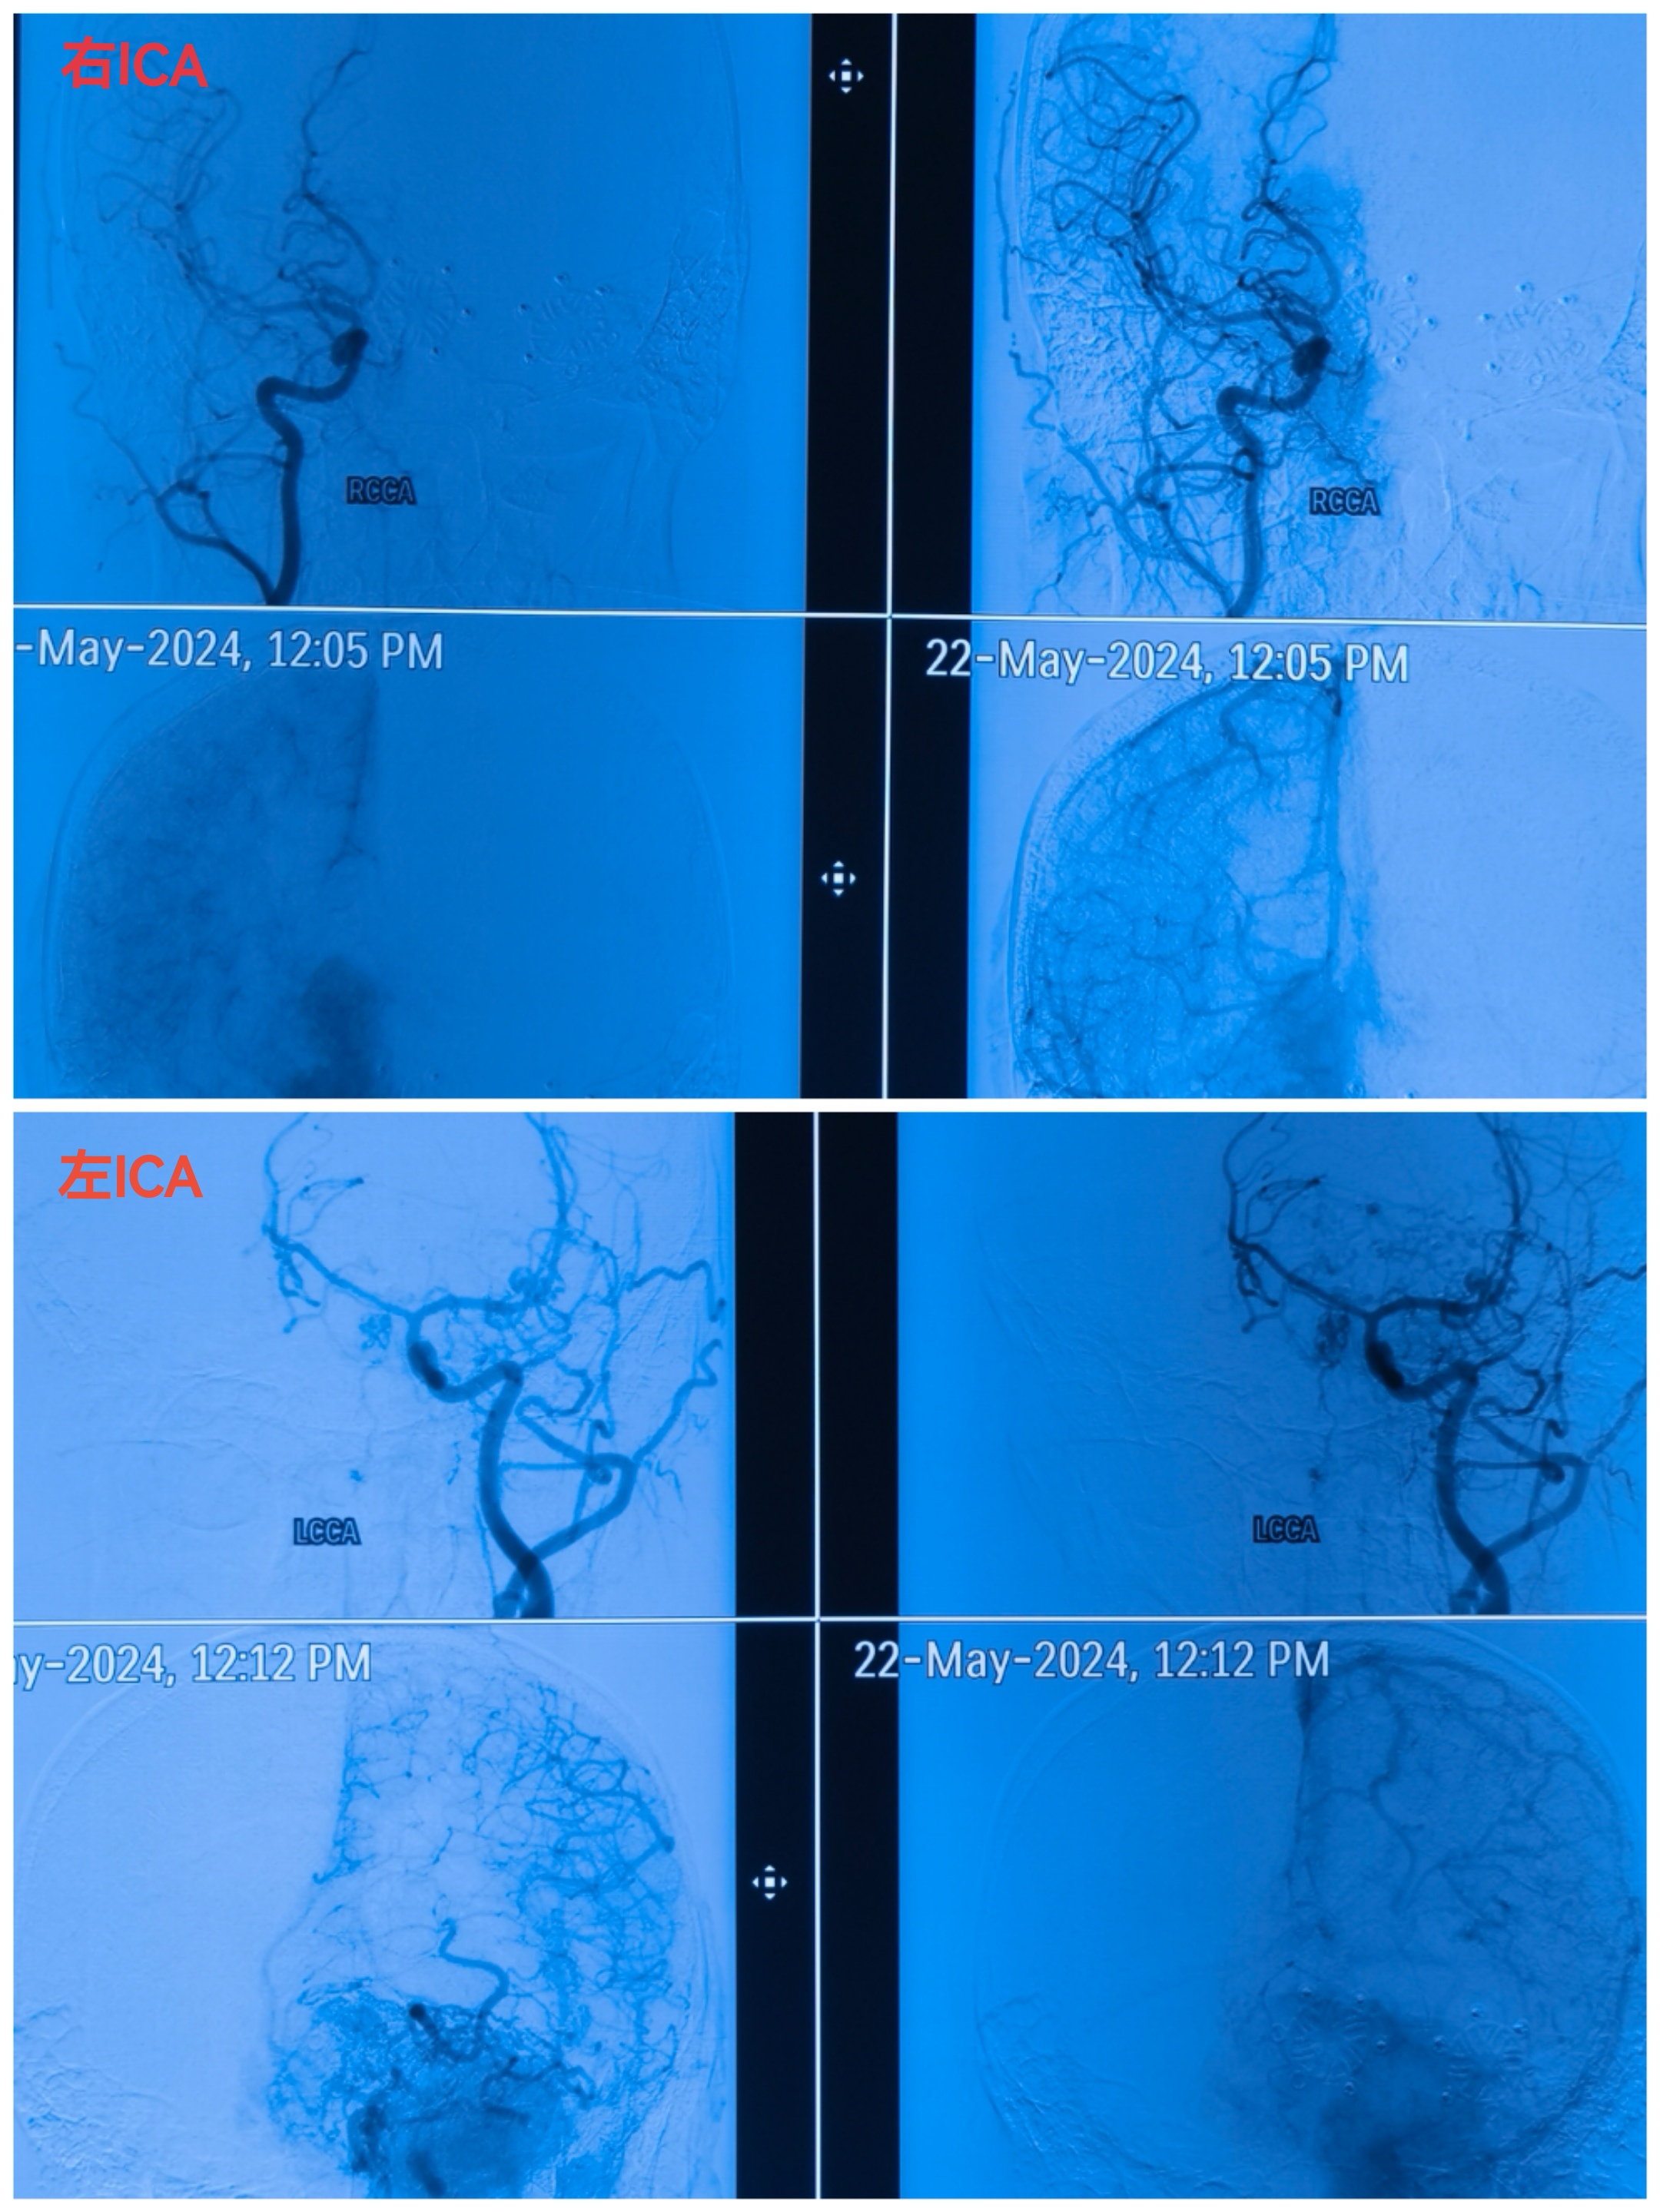

DSA显示肿瘤多支供血,染色明显。主要来自双侧大脑前及眼动脉(筛前后)和颈外少量供血。因为供血动脉纤细未行栓塞。

注意异常血管,以及双侧大脑前动脉的位置。

造影显示血管移位,肿瘤染色。